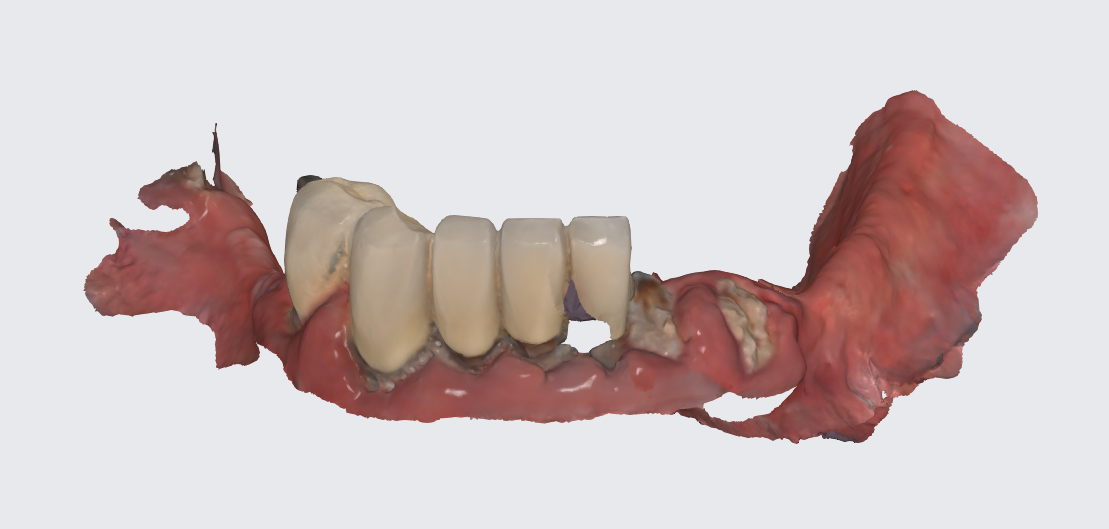

Since the surgeries took place on different appointments we decided to create interim dentures for the patient after each surgery, with the disadvantage that this flow of events would have to maintain the tilted position of the occlusal plane for the time being. For this to happen a scan of the previously operated jaw was performed.

This tray was used for border molding and analog impression and then scanned with a lab scanner as seen in the next photo.